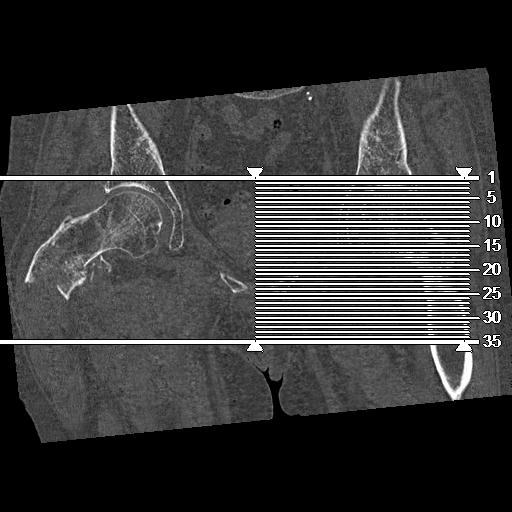

110286 2/17 股関節 2R 74歳女性 右人工骨頭

82084 1/14 1/20 股関節 2R 78歳男性 右人工骨頭

102811 1/13 股関節 2R 1/19 2R 80歳女性 右DHS